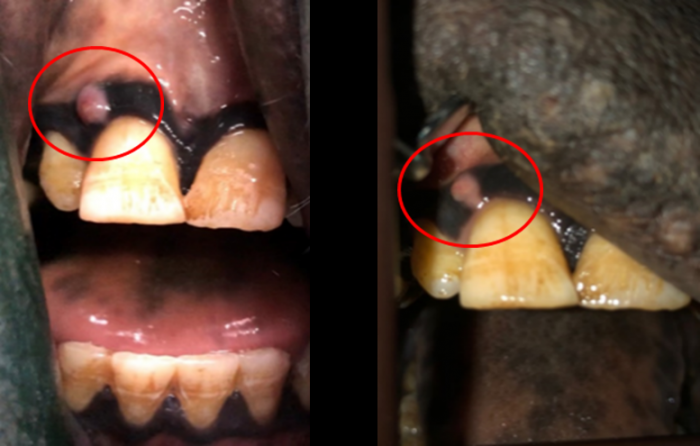

弟路郎の写真です。

その中でこの写真のように歯茎にでき物も発見し、経過を観察、徐々に小さくなって無くなることも確認したりしました。

レンボーから始め、弟路郎も完了。